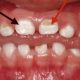

Enamel hypoplasia and decalcification can manifest as areas of altered color on primary dentition. These opacities, frequently observed as lighter shades than the surrounding tooth structure, represent variations in mineral content. They... Read more »